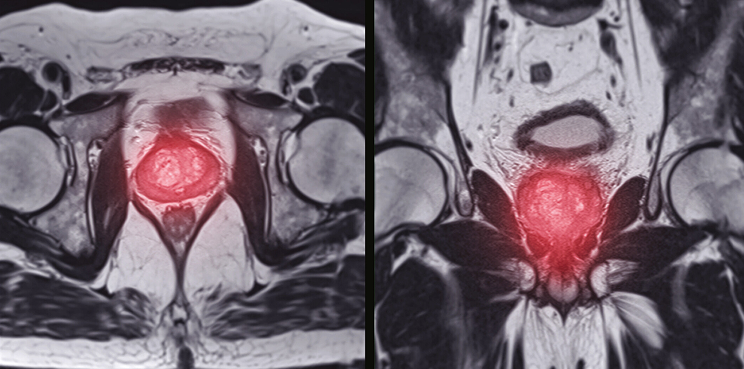

Traditional 2D medical imaging has its limits. With precise segmentation and 3D modeling, prostate cancer visualization becomes far more comprehensive. At Pareidolia, our advanced segmentation techniques allow for precise mapping of tumor boundaries, while our 3D modeling process converts these segmentations into realistic anatomical structures.

These 3D models assist AI algorithms and clinicians alike in:

- Understanding tumor morphology and spread.

- Comparing pre-treatment and post-treatment changes.

- Developing simulation-based diagnostic and treatment tools.